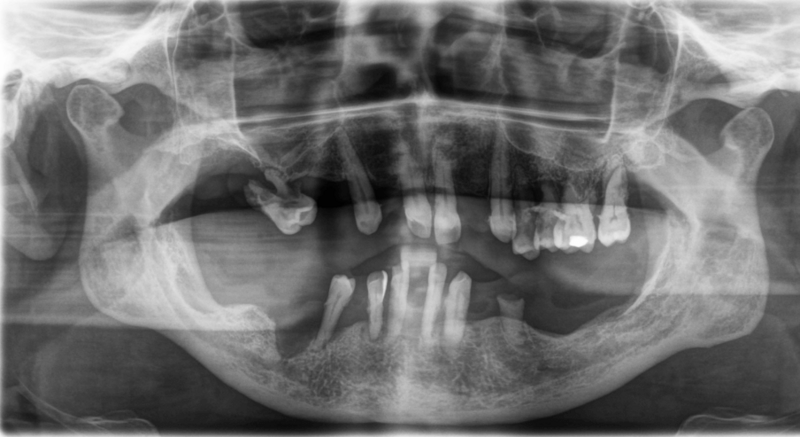

Die Prothesen waren durch Zahnsteinverblockungen und Gingivahyperplasien nicht mehr herausnehmbar.

OPG nach Entfernung von Zahnstein, Gingivahyperplasien und Prothesen (inklusive Zahn 47 ).